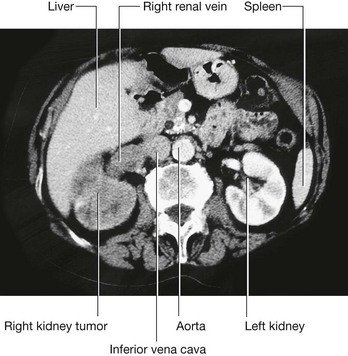

Renal cell tumors are unusual because not only do they grow outward from the kidney, invading the fat and fascia, but they also spread into the renal vein. This venous extension is rare for any other type of tumor, so, when seen, renal cell carcinoma should be suspected. In addition, the tumor may spread along the renal vein and into the inferior vena cava, and in rare cases can grow into the right atrium across the tricuspid valve and into the pulmonary artery (Figs. 4.142 and 4.143).

image

Fig. 4.142 Tumor in the right kidney growing toward, and possibly invading, the duodenum. Computed tomogram in the axial plane.

Fig. 4.143 Tumor in the right kidney spreading into the right renal vein. Computed tomogram in the axial plane.

Treatment for most renal cancers is surgical removal, even when metastatic spread is present, because some patients show regression of metastases.